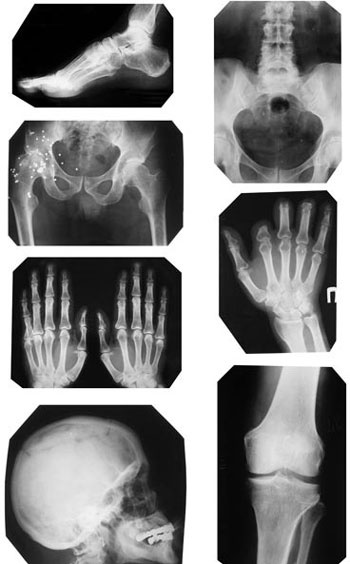

Рентгенография

Несмотря на широкое внедрение компьютерной томографии, значимым и информативным остается классическое рентгенографическое исследование.

Как правило, в поликлиниках его применяют на этапе скрининга: проще, быстрее и дешевле сделать рентгенограмму позвоночника, определиться, на каком уровне есть проблема, и затем исследовать пораженный участок прицельно с помощью магнитнорезонансного томографа.

Рентгенография остается эффективным информативным методом. С использованием ее хорошо диагностируются такие состояния, как заболевания позвоночника — дегенеративно-дистрофические (остеохондроз, спондилез, искривления), инфекционные и воспалительные (различные виды спондилитов), опухолевые заболевания. С успехом исследуются рентгенологически различные отделы периферического скелета — на предмет различных травматических (переломы, вывихи), инфекционных и опухолевых изменений. Степень тяжести остеоартроза и ревматоидного артрита определяется по рентгенологическим критериям — на рентгенограмме хорошо заметно состояние суставных поверхностей и степень остеопороза костей.

Иллюстрация к книге — Отложение солей. Диагностика и лечение [i_019.jpg]

Если суммировать преимущества рентгенографического исследования, они будут выглядеть так: